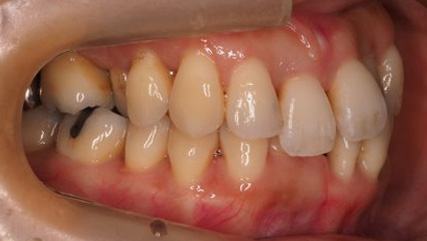

下顎が上顎より前に出ている状態です。お顔つきも、下顎の先(オトガイ)が前に出ているような横顔になる場合が多いです。前歯が咬んでいないことが多く、奥歯への負担が大きい状態になります。そのままのかみ合わせを続けてしまうと、奥歯がかけたり、割れたりするリスクが高まります。歯列矯正では奥歯の位置をコントロールし、前歯のかみ合わせを作る治療方針を立てます。ごく稀に、歯列矯正ではかみ合わせを作れない場合もあり、その場合は外科矯正という手段を用いて矯正治療をしなければいけません。受け口は、遺伝性が強いとも言われておりますので、そういった情報も考慮し、治療を進めていくことが大切です。

前歯が咬んでいない状態を言います。受け口同様、奥歯への負担が大きく、歯を失いやすい不正咬合と言われております。インビザラインでの治療の方が、ワイヤーを用いた治療より治療しやすい症例が多く、治療期間はワイヤー治療に比べて比較的短期間になることが多いです。出っ歯、同じように口呼吸、舌の位置が悪い、口が閉じれないなどの症状を伴うことが多いので、そういった点も考慮して治療していく必要があります。

治療前

治療終了前